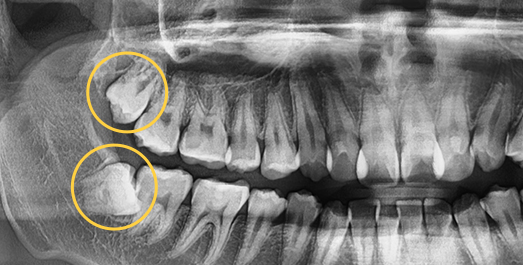

Complex wisdom tooth cases, Seoul The Nature Dental Clinic

does not give up.

Even advanced cases

can be extracted.

With extensive experience in numerous advanced cases and a wide range of wisdom tooth extractions, you no longer need to go to a university hospital.